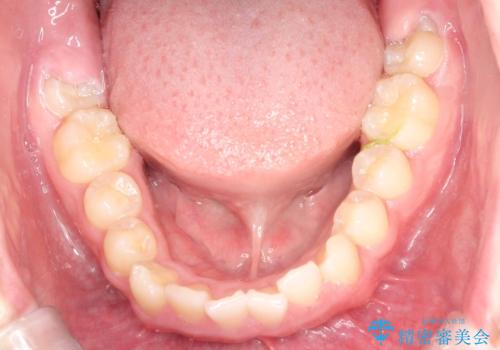

八重歯・歯並びのデコボコとディープバイトを改善した抜歯ワイヤー矯正症例

- 八重歯と咬み合わせを治したいを主訴にご来院された患者様です。

矯正の精密検査の結果上顎左右4番の計2本を抜歯し、審美性に配慮したワイヤー矯正装置(審美装置)を用いて治療を行いました。

八重歯などの歯列のデコボコが綺麗に改善され、患者様にも大変喜んでいただけました。また、咬み合わせが深い「ディープバイト」も併せて改善し、見た目だけでなく機能面でもバランスの取れた咬合を獲得しています。